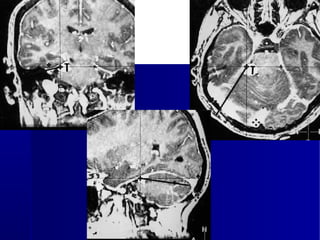

NEURONAVEGAÇÃO

Advances in Surgery l September 9, 2006 l 51

Como minimizar riscos e

maximizar a ressecção ?

Neuronavegação

Mapeamento Funcional

Imagem Intraoperatória